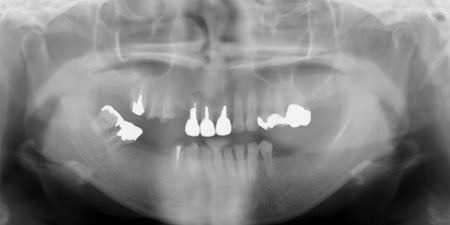

43歳 女性

主訴 奥歯で物が咬めない

治療内容 歯周病治療 咬合治療 インプラント治療 歯内治療(根の治療)

治療前